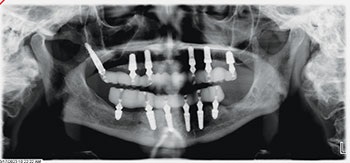

Our patient, a healthy woman in her early 60s, presented with a terminal dentition (Fig. 1) in both arches, collapsed bite, unstable occlusion, midline shift, asymmetric horizontal plane and bone loss (Fig. 2). She was looking for a fixed solution that would give her the confidence to smile, eat and socialize without restrictions. Several previous treatment plans suggested placing provisional dentures as an interim until the implant stabilized, which did not resonate with her desires during the healing phase.

Fig. 1

Fig. 2

Surgery was uneventful. Extractions, site preparations and implant placements went according to plan (Fig. 3). In the maxilla, we placed six implants following the “All-on-6” concept, ensuring posterior spread for optimal load distribution. Six implants were also placed in the mandible following a similar approach.

All implants achieved excellent primary stability (>35 Ncm Torque and ISQ values averaging 72 to75), which allowed us to proceed with immediate loading (Fig. 4). Using SprintRay 3D printed provisionals in OnX Tough 2 resin, we delivered fixed temporaries the next day post-surgery (Figs. 5–8).